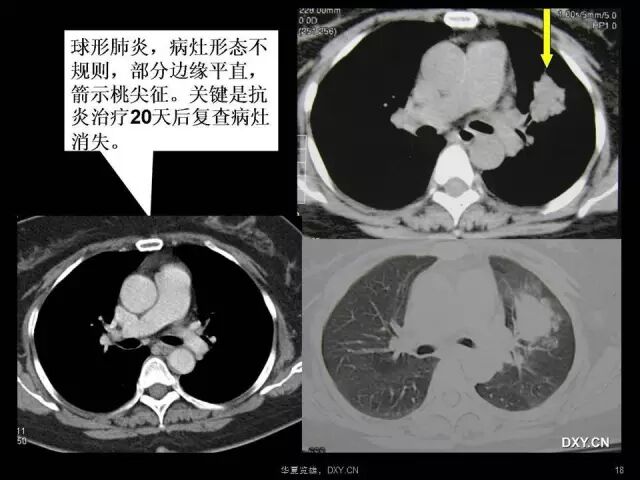

肺炎、肺癌、肺结核在影像学上的征象往往千变万化。